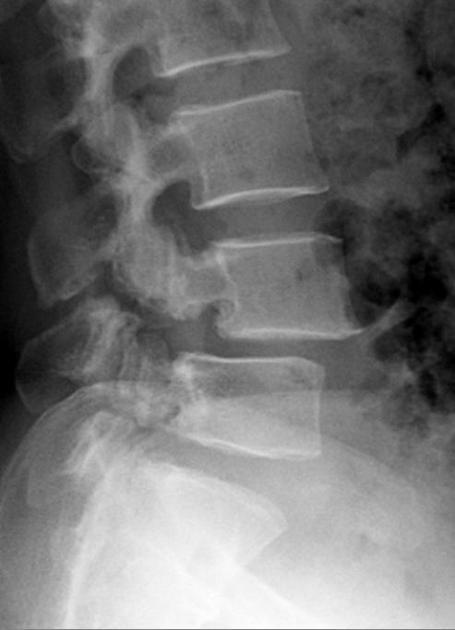

Spondylolistéza (olistéza = posun, skĺznutiu) je sagitálny posun stavca dopredu voči susednému, nižšie umiestnenému. Vzniká najčastejšie v bedrovokrížovej oblasti chrbtice.

Príčinou je porušený vývoj (osifikácie) oblúka, alebo pretrvávajúca mikrotraumatizácia a následné prerušenie isthmu - spondylolýza - tzv. Istmická spondylolistéza (najčastejšie L5-S1), alebo následkom nestability u starších pacientov - degeneratívne spondylolistéza, typicky L4-5, ďalej aj zriedkavo úraz, zápal, alebo tumor.